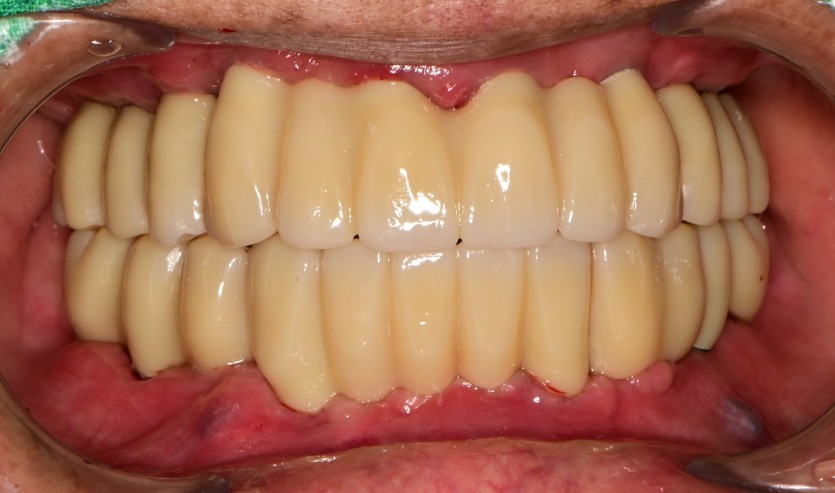

전체 임플란트 증례입니다.

18개의 임플란트로 완성하였습니다.